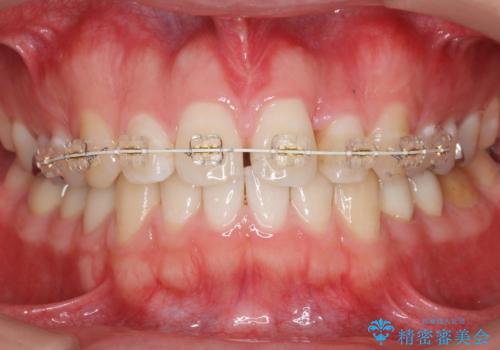

前歯のねじれ 上だけ部分矯正でコストダウン

- 矯正装置

- 審美装置

- 前歯のねじれを部分矯正で治療しました。

奥歯のかみ合わせを変えずに、費用を抑えて短期間に治療したい方におすすめです。

矯正前に、後戻り防止のため上唇小帯の処置を行っています。